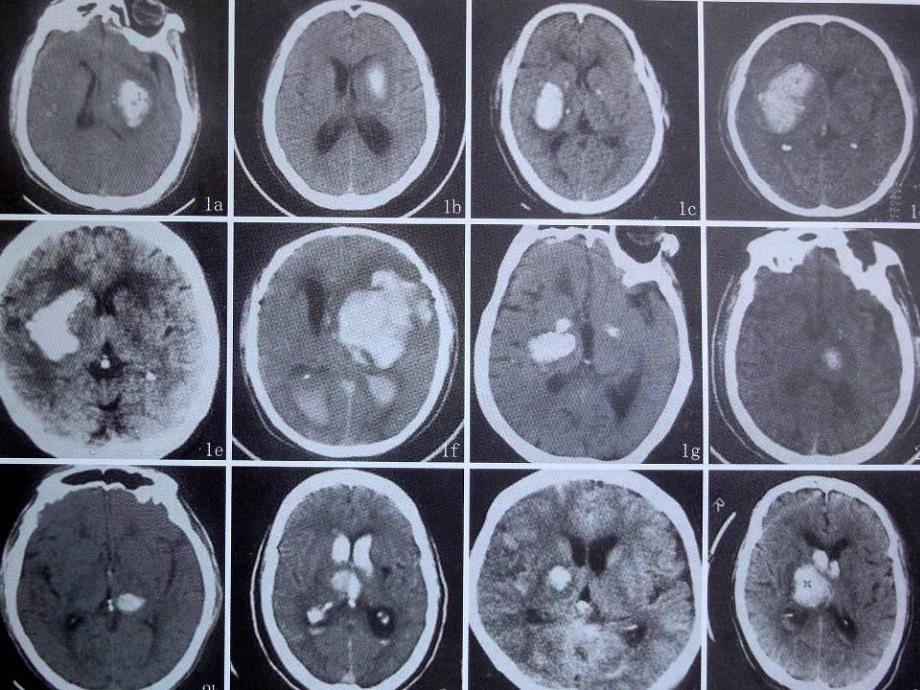

4、病各疾病治疗治疗方案不一方案不一,预后不一致预后不一致,家属期望质不一致家属期望质不一致。五、五、高血压脑出血高血压脑出血(HCH;HICH)HCH;HICH)为什么要进行临床分类、分级为什么要进行临床分类、分级:便于交流便于交流;教学教学;提醒医师对病情注意和即时处理提醒医师对病情注意和即时处理。六、六、高血压脑出血诊断依据:高血压脑出血诊断依据:高血压脑出血目前主要是依靠检查高血压脑出血目前主要是依靠检查-CT,MRI 其它其它 如腰穿如腰穿;A造影造影七、高血压脑出血七、高血压脑出血CT扫描表现:扫描表现:1.脑内血肿的脑内血肿的CT表现主要为血肿本身影像,呈占位表现。新鲜血肿与表现主要

5、为血肿本身影像,呈占位表现。新鲜血肿与脑边界清楚,高密度区,脑边界清楚,高密度区,CT值为值为6080H。血肿周围可见到低密度。血肿周围可见到低密度水肿带围绕。水肿带围绕。2.CT显示血肿与脑水肿引起的脑室、脑池、脑沟受压和中线结构移位显示血肿与脑水肿引起的脑室、脑池、脑沟受压和中线结构移位等表现。血肿可破入脑室或蛛网脉下腔,在相应部位有高密度区。等表现。血肿可破入脑室或蛛网脉下腔,在相应部位有高密度区。积血可见于一侧或两侧侧脑室或全部脑室。积血可见于一侧或两侧侧脑室或全部脑室。3.发病发病37天后,血肿边缘高密度血肿边缘变得模糊,周边低密度区天后,血肿边缘高密度血肿边缘变得模糊,周边低密度区

6、增宽,高密度向心性缩小,血肿的增宽,高密度向心性缩小,血肿的CT值减低。值减低。1月后血肿成为等密度或低密度灶。月后血肿成为等密度或低密度灶。2月后血肿完全吸收。月后血肿完全吸收。附:1八、八、CT 在在HCH中应用价值中应用价值:1.HICH的病人首选的病人首选CT检查,它既安全可靠又无创伤且对检查,它既安全可靠又无创伤且对HCH的病因诊断有定位和定性价值。相距时间越短阳性率的病因诊断有定位和定性价值。相距时间越短阳性率越高,否则相反。越高,否则相反。2.CT显示出血密度高低有显示出血密度高低有Hb决定,决定,Hb小于小于100g/L可表现为可表现为等密度。等密度。一般认为一般认为CSF细胞

7、总数达细胞总数达2000个个/mm3以上者,以上者,CT扫描呈高密度影,出血扫描呈高密度影,出血2周以上者高密度影消失。周以上者高密度影消失。便携式便携式CT九、九、HCH-CT示血肿形态对临床评价示血肿形态对临床评价 1.不稳定型不稳定型-不规则型不规则型 (手术不好做手术不好做,岀血多岀血多,残血多残血多)2.稳定型稳定型-规则型规则型 (手术易手术易,残血少残血少)注注 1.不稳定型不稳定型HCH血肿血肿,异常血管团达异常血管团达1/3,手术所见血手术所见血管异常丰富管异常丰富,病检不构成病检不构成AVM;2.不稳定型不稳定型HCH血肿血肿,血压血压200mmHO,血肿扩大血肿扩大1/3

8、.3.不稳定型不稳定型HCH血肿血肿,6H24H内内,血肿扩大血肿扩大1/3.4.不稳定型不稳定型HCH血肿血肿,肝功能不好肝功能不好,血肿扩大血肿扩大1/3.手术前手术前手术后手术后稳定型稳定型手术前手术前手术后手术后稳定型稳定型不稳定型不稳定型手术前手术前手术后手术后稳定型稳定型手术前手术前手术后手术后不稳定型不稳定型不不稳稳定定型型手术前手术前手术后手术后不稳定型不稳定型手术前手术前不稳定型不稳定型手术后手术后不稳定型不稳定型手术前手术前手术后手术后十、十、MRI在脑内血肿中表现在脑内血肿中表现-按时间可分为按时间可分为5期期1.超急性期(超急性期(30ml为为1分分;80岁为岁为1分分